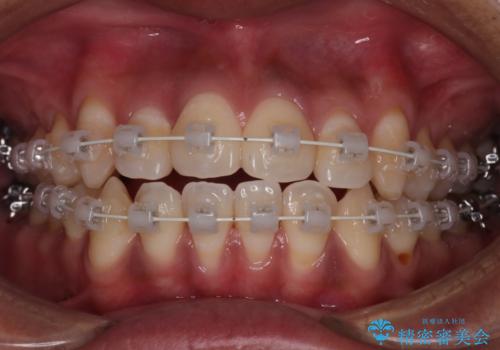

【審美装置】開口(オープンバイト)を改善

- 矯正装置

- 審美装置

- 全体的に歯並びをよくしたいとのことで来院されました。初診時、患者様はセラミック矯正とワイヤー矯正で迷われていました。

開口(オープンバイト)のため噛み合わせを考慮してワイヤー矯正を提案させていただきました。

IPR(歯と歯の間を削る処置)と顎間ゴムを行い歯並びを整える治療計画を立てました。